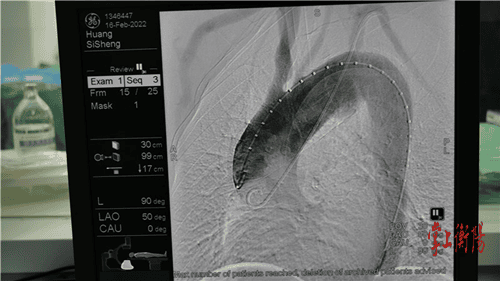

据悉,患者所患的是胸主动脉假性动脉瘤,病变累计供应头颅血运的弓部主动脉,随时有血管破裂大出血死亡风险,这种疾病是血管外科最为凶险、复杂的疾病。常规的开放手术需要开胸及体外循环,创伤大、并发症发生率高,对患者损伤较大。若采用介入技术,患者的弓动脉瘤足足有3公分大,由于弓部有重要分支血管,腔内治疗面临着巨大的挑战,稍有差池都可能影响大脑血供、导致脑梗等严重后果。最终,南华附二医院血管外科团队经过反复推敲和论证,在上海长海医院专家的远程会诊指导下,决定采用体外预开窗的方式,术前根据影像资料确定病变部位与分支血管之间的关系,体外将预制支架部分释放,精准定位后在支架上预先开好两个窗用来重建颅内两分支血管,术中准确释放支架,保证支架和窗口的精确对应,保障大脑血运不受影响。

最终,手术历时近3个小时,顺利为患者放入了覆膜支架,隔绝了胸主动脉弓部的“炸弹”。此次远程手术中,协调指导几乎完全同步,手术过程中网络零延时,来自上海的专家仿佛亲临现场指导一样,效果很好。手术的成功实施,让患者避免了开胸手术带来的损伤,也减少了医疗费用,加速了患者的术后康复。